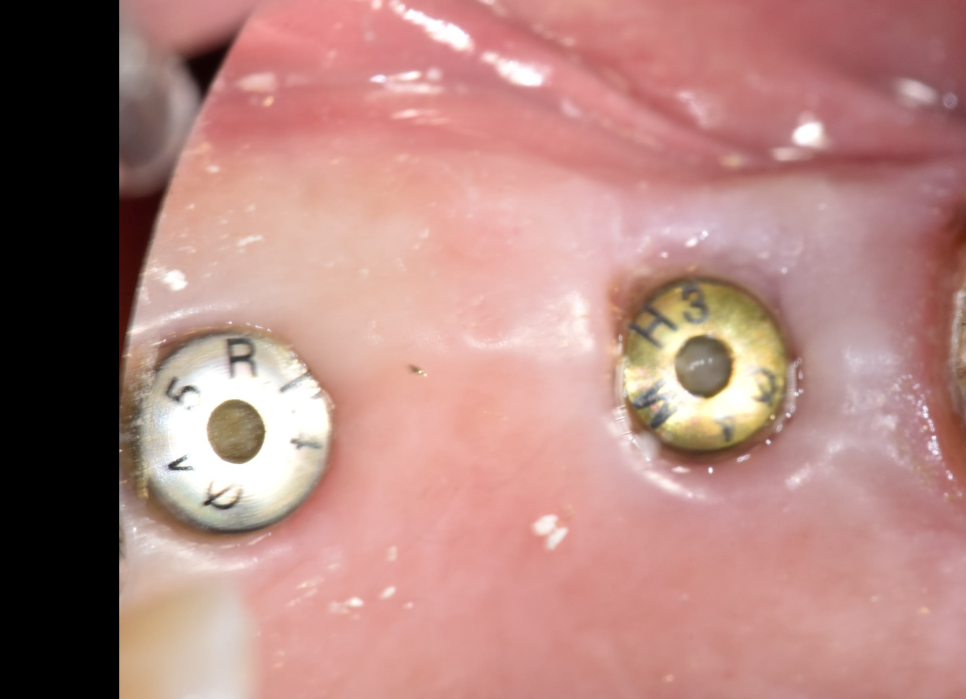

다음날 오셧을때의 사진입니다. 깔끔하게 다 아물었네요.

이제 최종보철물을 올리고 씹으시면될것같습니다.